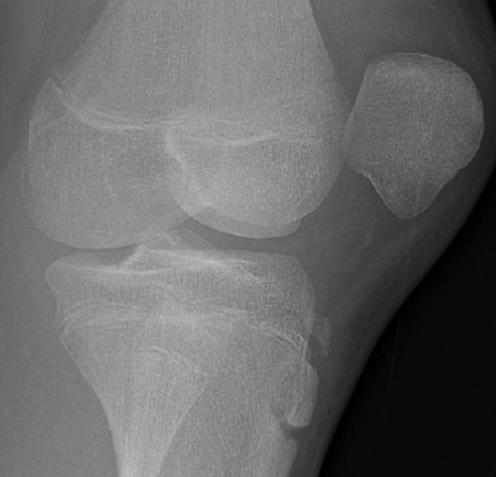

X-rays are often used to confirm a dislocated patella. If the individual presents with a history of first-time patellar dislocation that has already been relocated, X-rays may not be helpful.